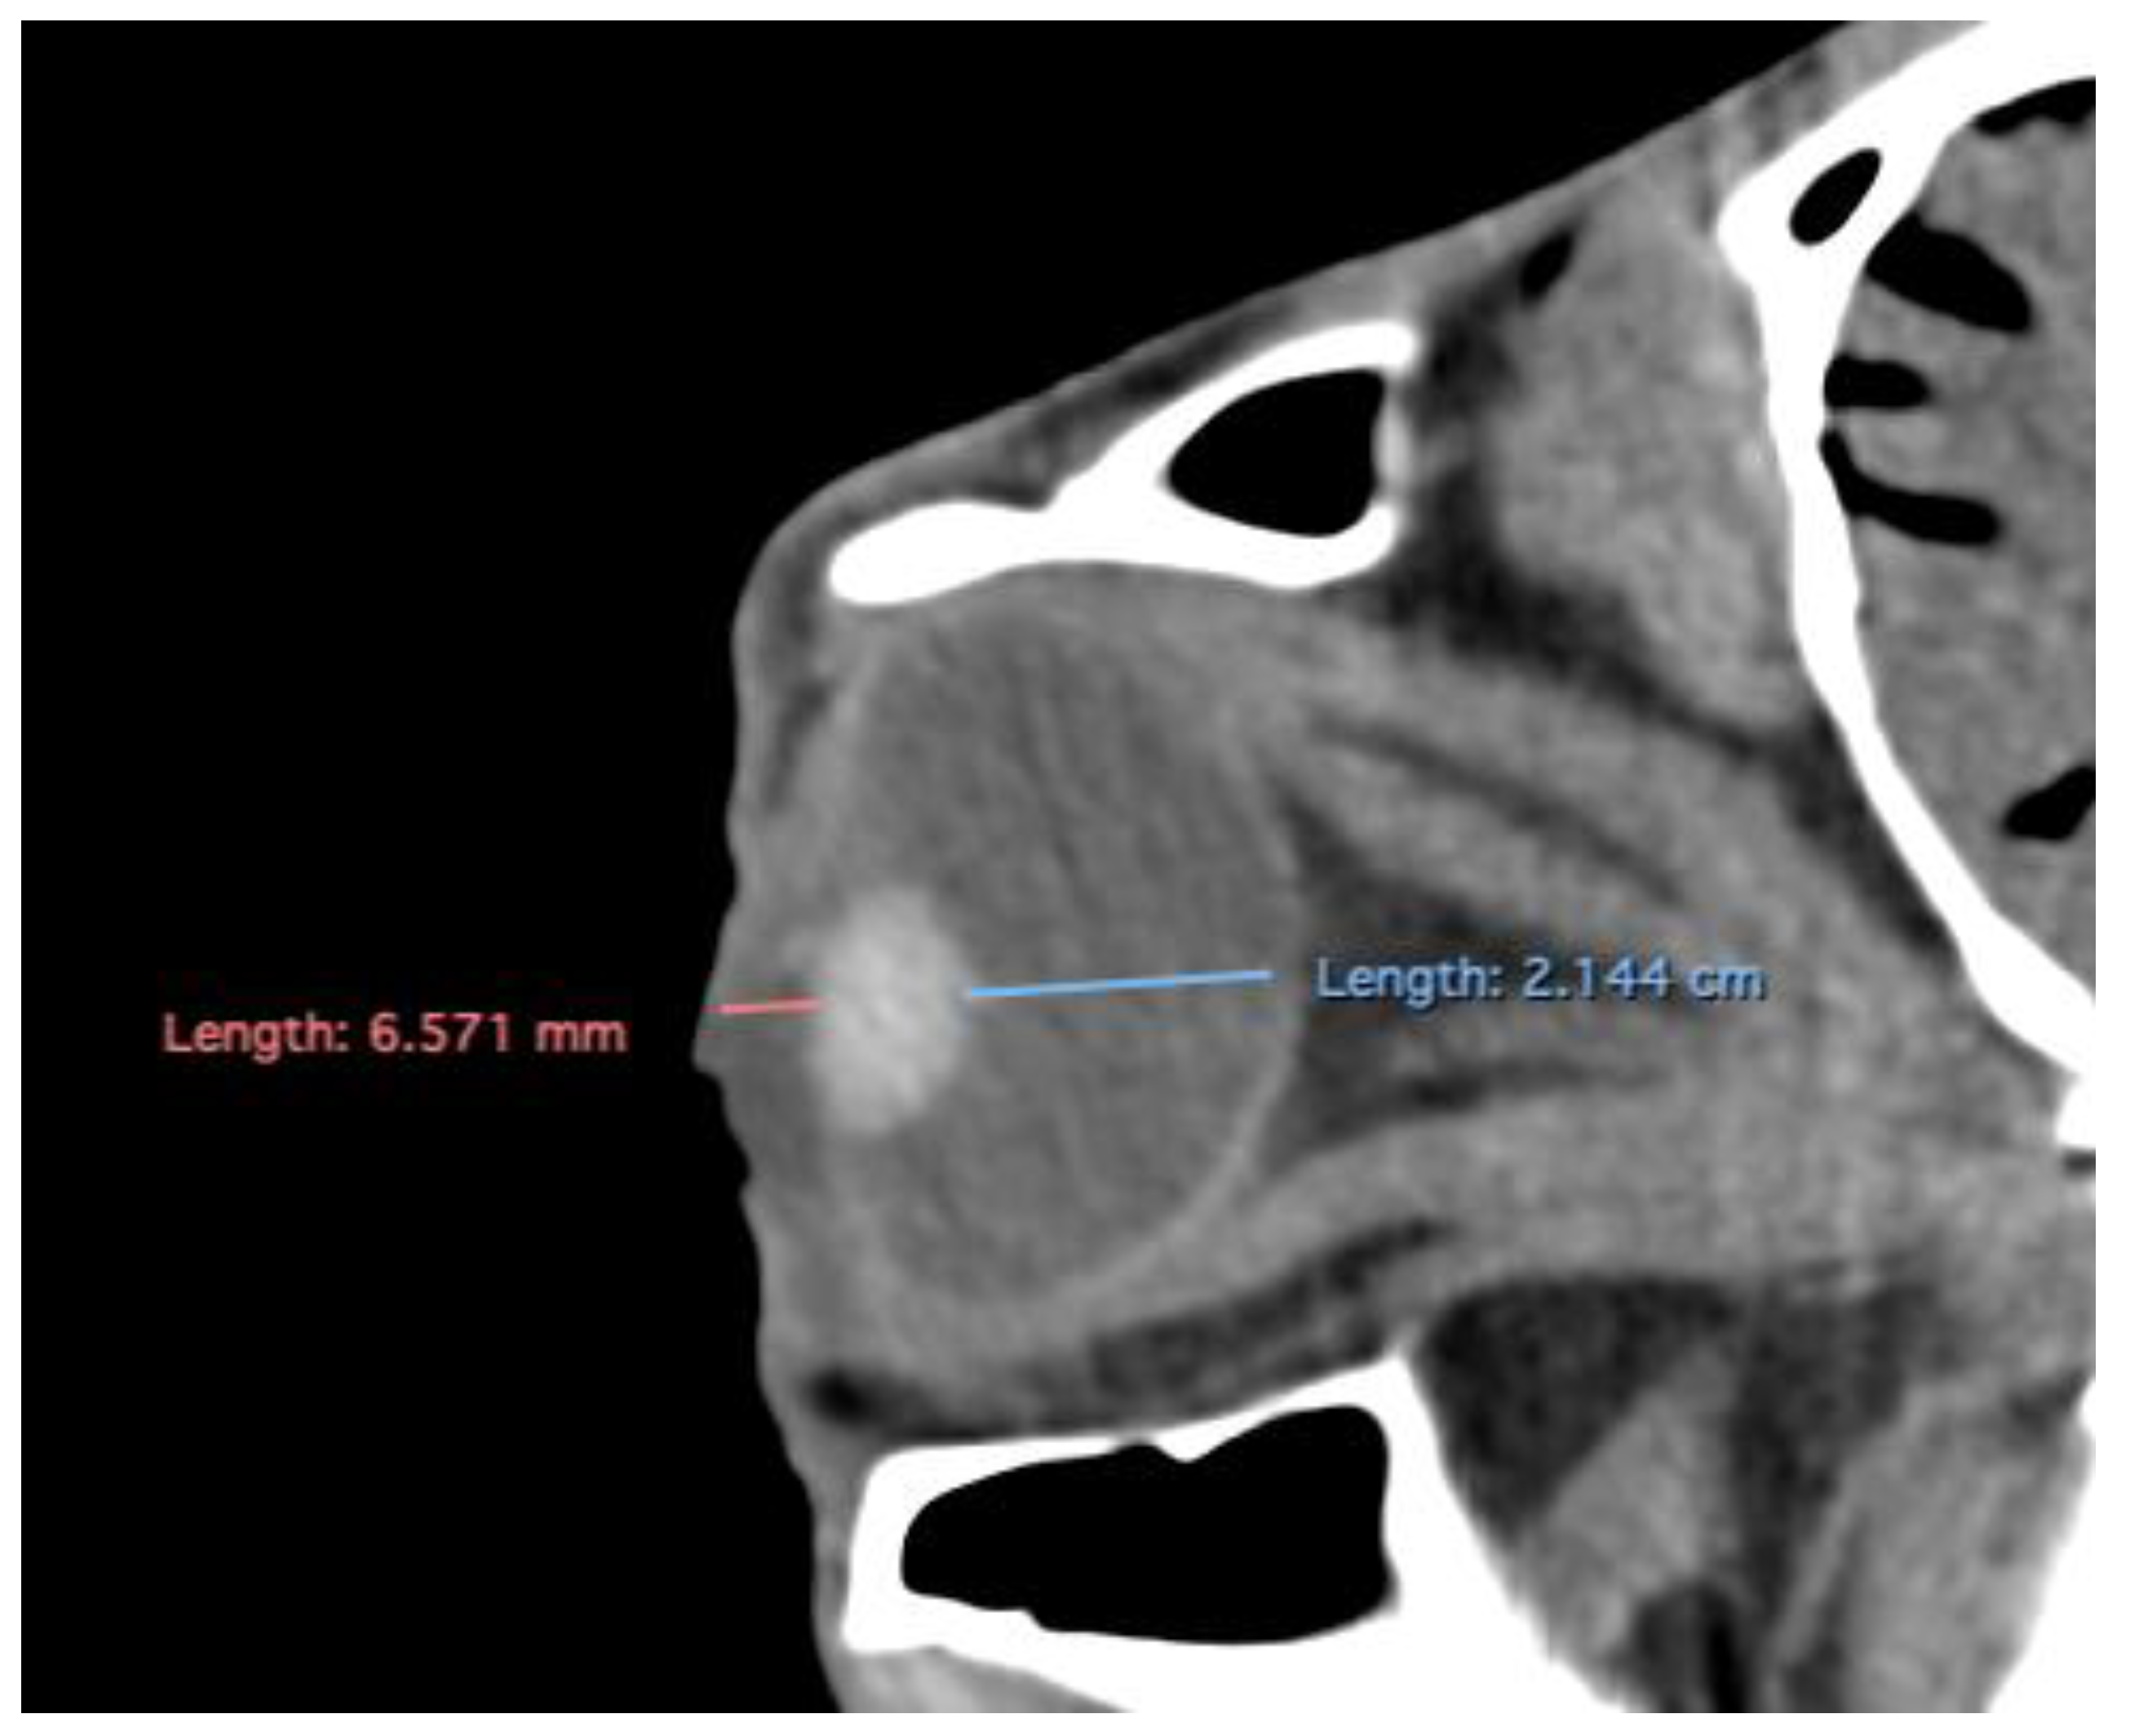

- Anterior chamber, posterior chamber, and lens densities: Attenuation values measured by placing regions of interest (ROIs) centrally in each structure (Figure 3).

- Anterior and posterior chambers width: Maximal lateromedial distance across the anterior and posterior chambers. (Figure 5)